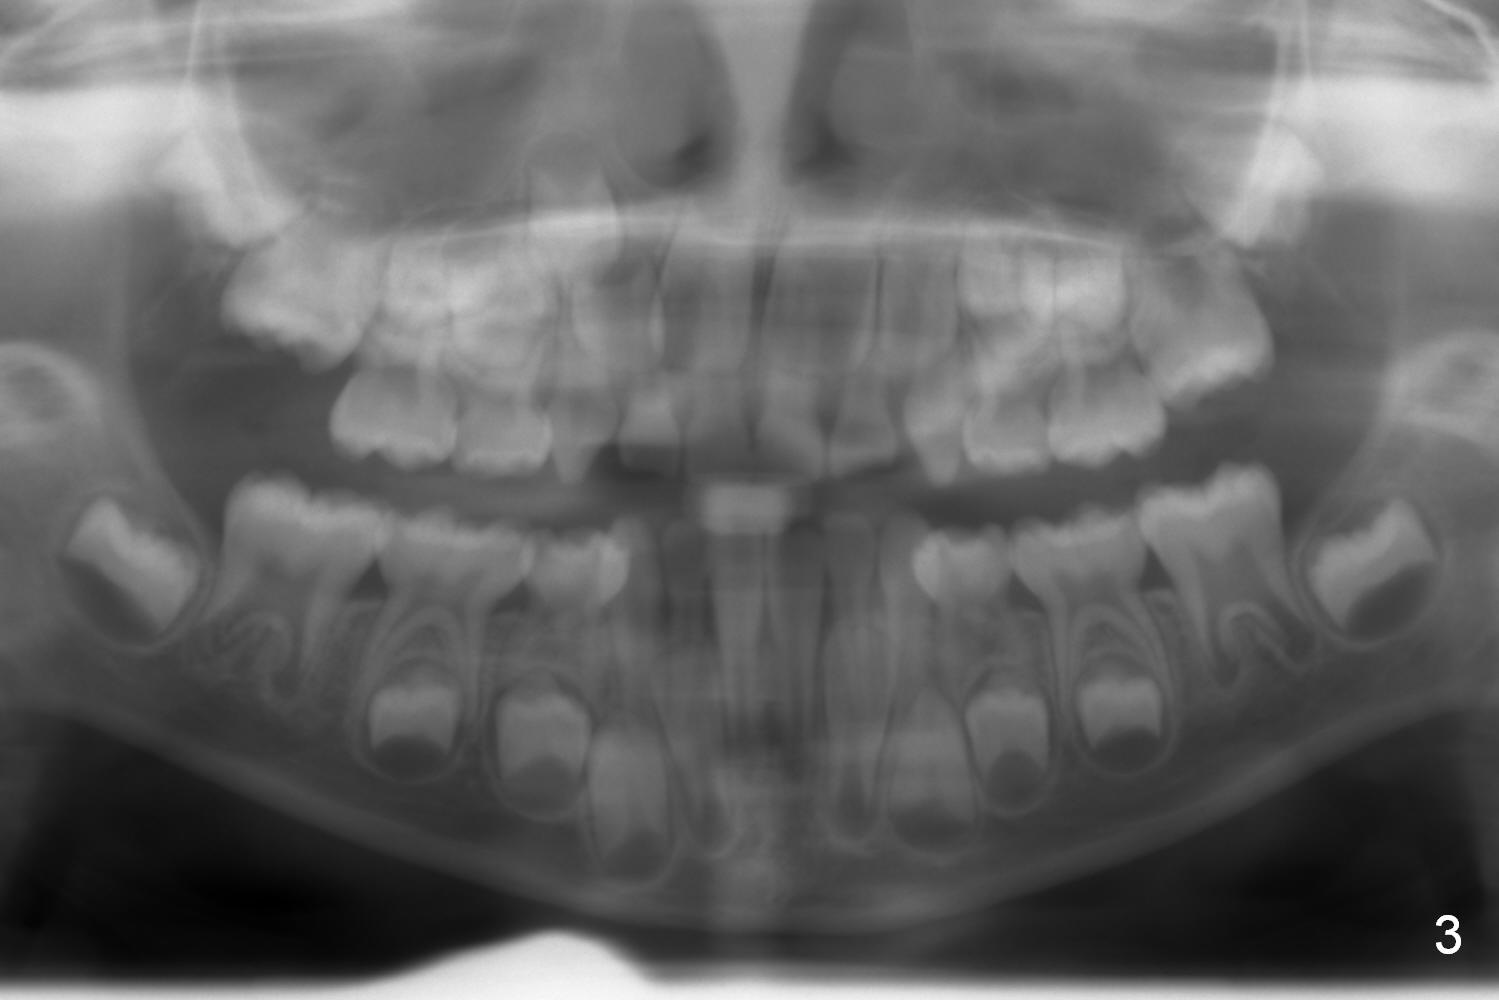

Deciduous Anterior Cross Bite

Unlike his brother, Andrew (7 years 10 months old) does not have missing teeth (Fig.1-3). But there is anterior cross bite involving the deciduous teeth (Fig.2: B, C). It appears that the permanent lower central incisors (Fig.1: #1) have erupted into the normal position (Fig.2). It is hoped that the anterior cross bite is a temporary phenomenon.